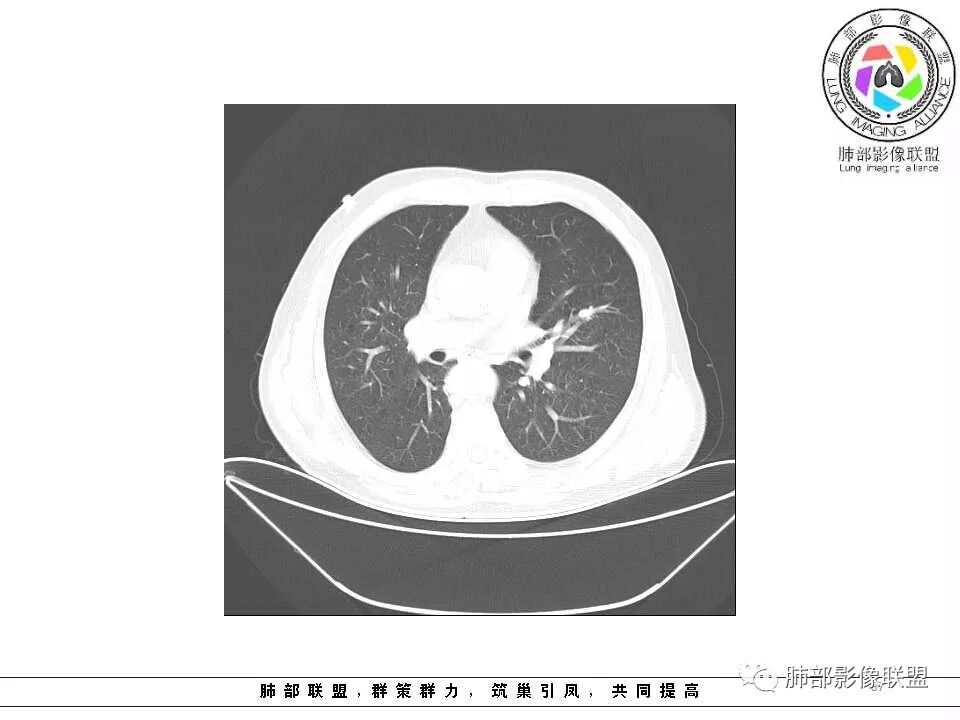

影像学特点:肺气肿背景下在大概一年的时间里出现了一个光滑的小结节,因为图像给的不是太薄,与支气管的关系判断不清,从结节周围出现斑片状炎症来判断,应该考虑结节位于支气管内,周围是阻塞性炎症,这样比较容易解释咯血

老年男性,左肺舌段见多个小结节灶及斑片状高密度灶、磨玻璃影,结节灶边界清晰,光滑,无明显分叶,密度均匀,周围病灶密度不均,一年内生长,考虑恶性肿瘤并阻塞性肺炎出血,小细胞可能大。

左肺上叶小结节病灶,形态规则,边缘光滑,密度至密,远处阻塞性肺炎,病灶与支气管关系密切,给图太少不好观察,考虑神经内分泌癌(类癌),其次鳞癌

老年男性,肺气肿基础。约一年时间出现左肺上叶舌段支气管近端结节影,远端斑片样阴影,边缘模糊。考虑近端恶性占位,远端有阻塞性炎症。

老年男性,有咳血病史,左肺上叶舌段一年时间出现新发类圆形小结节,感觉在支气管内,部分凸出气管外,没有mpr不好说,远端肺野斑片模糊影,考虑阻塞性炎症,纵隔无明显肿大淋巴结,小细胞代排,按照发展速度,类癌低度恶性,应该发展缓慢,一年病史,代排,首先考虑鳞癌并阻塞性炎症

肺气肿背景,2016年左肺上叶上舌段见微结节,2017年5月左肺结节增大,密度均匀,边缘光滑锐利,与邻近血管关系密切,血管贴壁走行,外侧见尖状突起,下舌段片状影,沿着支气管走行,内有粘液栓,考虑鳞癌,鉴别小细胞肺癌。

肺气肿背景,2016年左肺上叶上舌段见微结节,一年后左肺结节增大,密度均匀,边缘光滑、膨隆,似见小分叶,下舌段片状影,沿着支气管走行,内,老年患者,咯血1月。考虑恶性病变并阻塞性肺炎,鳞癌?注意鉴别结核。

老年男性,咯血1月,肺气肿背景,16年左肺上叶舌段结节,左肺门疑似淋巴结肿大,呈结节感。17年左肺上叶舌段见沿支气管走行分布结节 远端阻塞性肺炎,左肺门淋巴结肿大明显,首先考虑恶性病变,鳞癌?类癌?

前次片2016年4月20相应位置就有小点状病灶,2017-5-15呈结节影改变,边界膨隆,远端阻塞炎性改变,考虑肺癌,鉴别炎性结节!